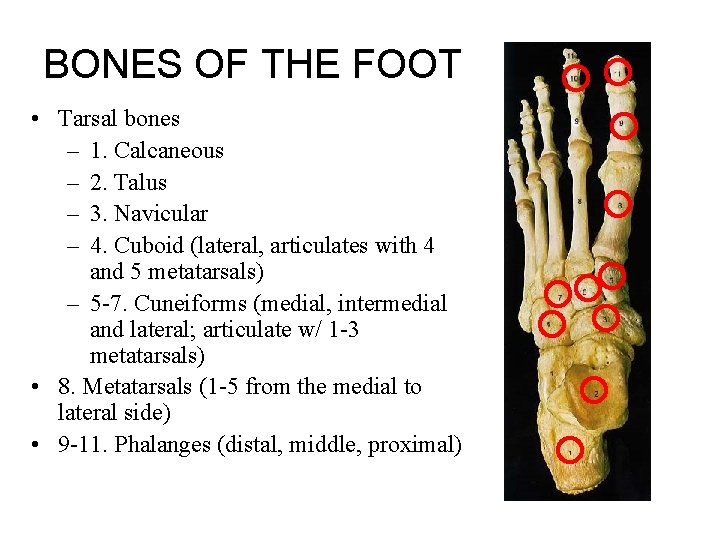

BONES OF THE FOOT • Tarsal bones – 1. Calcaneous – 2. Talus – 3. Navicular – 4. Cuboid (lateral, articulates with 4 and 5 metatarsals) – 5 -7. Cuneiforms (medial, intermedial and lateral; articulate w/ 1 -3 metatarsals) • 8. Metatarsals (1 -5 from the medial to lateral side) • 9 -11. Phalanges (distal, middle, proximal)

• Tarsal bones • 1. Calcaneous • 2. Talus • 3. Navicular • 4. Cuboid (lateral, articulates with 4 and 5 metatarsals) • 5 -7. Cuneiforms (medial, intermedial and lateral; articulate w/ 1 -3 metatarsals) • 8. Metatarsals (1 -5 from the medial to lateral side) • 9. Phalanges